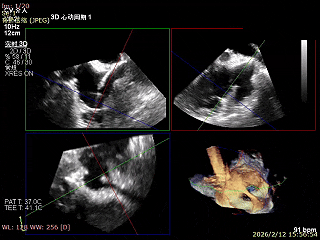

手术效果评估

反流评估:术前4+下降至1+

术前中央反流

术后中央反流

DSA双夹释放后形态无异常,锚定部位均在预期位置,RCA血流未受到影响。

后复查经胸心脏超声,示肺静脉、肝静脉逆流消失,二尖瓣及三尖瓣反流降低至轻度,手术效果良好。